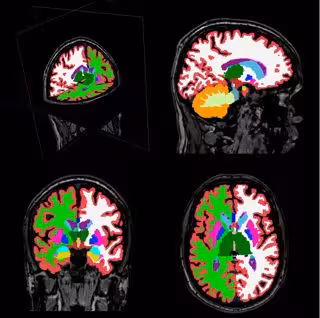

Para solventar estos problemas e intentar clarificar el tipo de anomalías estructurales cerebrales presentes en la esquizofrenia, se ha llevado a cabo un innovador meta-análisis prospectivo que analiza datos de imagen cerebral obtenidos mediante resonancia magnética. Se trata del mayor estudio colaborativo de imagen cerebral en pacientes con esquizofrenia realizado hasta la fecha, en palabras de Benedicto Crespo Facorro, psiquiatra del Hospital Universitario Marqués de Valdecilla (HUMV), profesor titular de la UC y director del Laboratorio de Neuroimagen del IDIVAL.

En este estudio, en el que se incluye muestra de psicosis PAFIP, se analizaron datos de resonancia magnética cerebral de 2.028 pacientes con esquizofrenia y 2.540 individuos sanos obtenidos mediante métodos estandarizados en 15 centros de investigación de diferentes países.

En comparación con los controles, los pacientes con esquizofrenia mostraron una disminución en el volumen del hipocampo (estructura asociada con la memoria), la amígdala (estructura asociada con la emoción), el tálamo (asociado a la actividad sensorial) y del núcleo acumbens.

Asimismo presentaron un aumento en el volumen del pállidum (involucrado en la motivación y la emoción) y de los ventrículos laterales. Además, se encontró una asociación entre los volúmenes del putamen y del pállidum y la duración de la enfermedad y que el déficit en el volumen del hipocampo era más severo en las muestras con mayor proporción de pacientes sin medicar. Esto sugeriría, según Crespo-Facorro, que "el tratamiento con antipsicóticos podría aminorar la pérdida de volumen en el hipocampo".